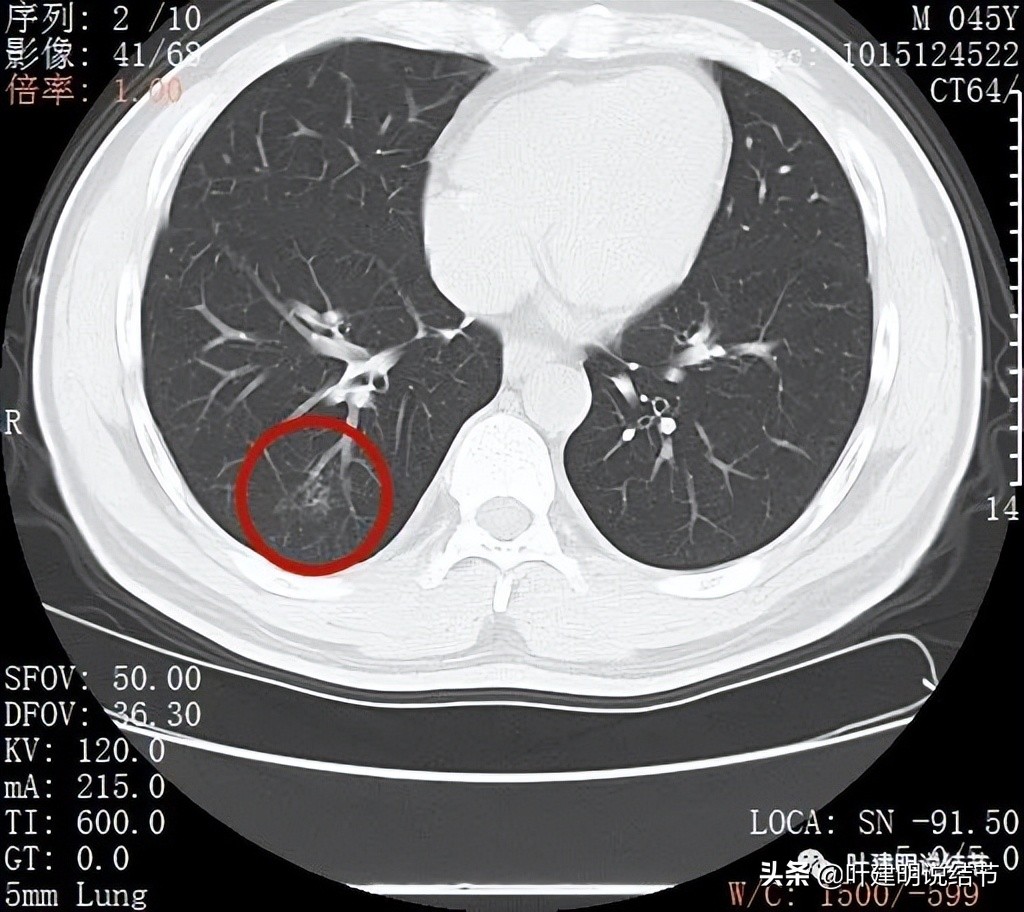

再来看薄层扫描:

病灶感觉很散在,但内部有扩张的细支气管(黄色箭头)、边缘略显不清(绿色箭头),部分有偏实性(粉色箭头)。

边缘血管异常增粗(桔色箭头),边缘显糊(绿色箭头),细支气管扩张(黄色箭头)